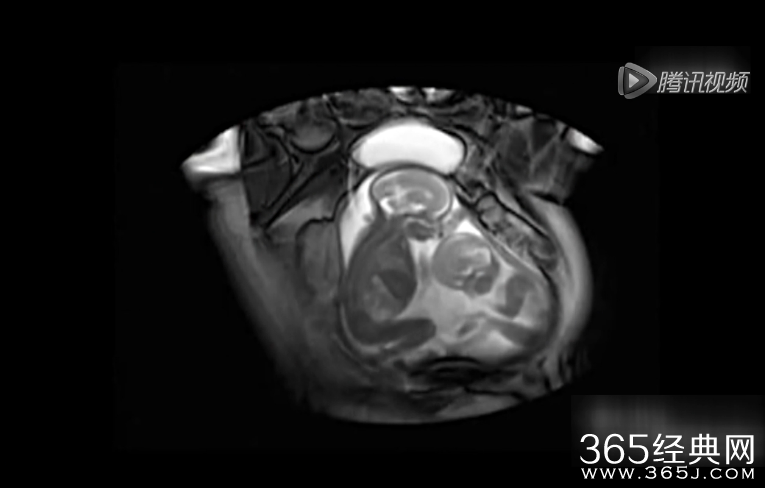

365经典网 左边的姿势舒服,右边的表示抗议,左边是文的嘴在动,右边是武的用脚蹬,这样妈咪真的没反感觉么?大家都看见小的打打的,有没有看见大的让小的呢,不过我看见大的嘴动了吗?